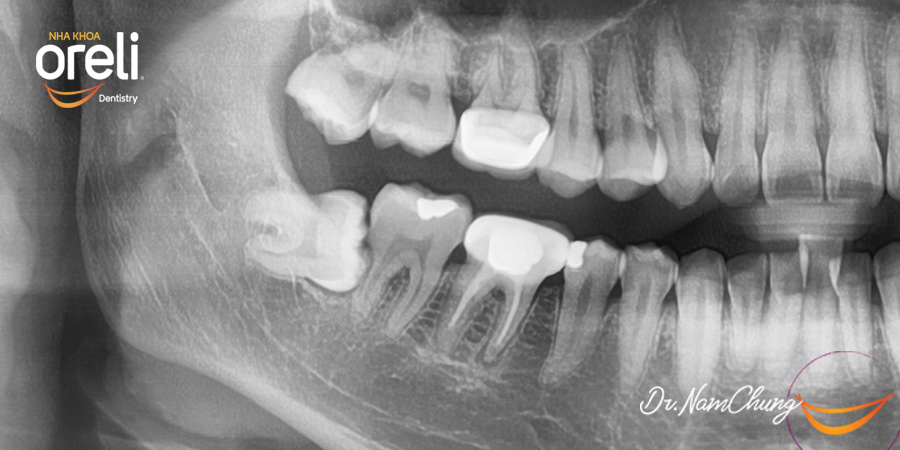

Nhổ răng khôn hàm dưới mọc lệch – Ca thực tế tại Oreli Buôn Ma Thuột

Nhổ răng khôn

Mọc lệch

Xem thêm